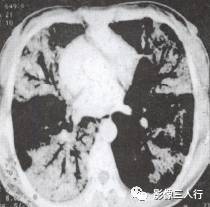

胸部CT图像显示,在含气少的致密肺的背景上见到含气的支气管,表现为两种形态: ①在大片肺实变病灶内的细条状空气密度影;②直径Imm的小泡状空气密度影,连续的几 个层面都能出现(图2、图3)。该征象表明:①近侧气道通畅;②肺泡内的空气经吸收(肺不张)或取代(肺炎、肺癌),或两者综合而消失。通畅含气的支气管在肺泡实变高 密度区内表现为管腔内低密度充气轮廓。